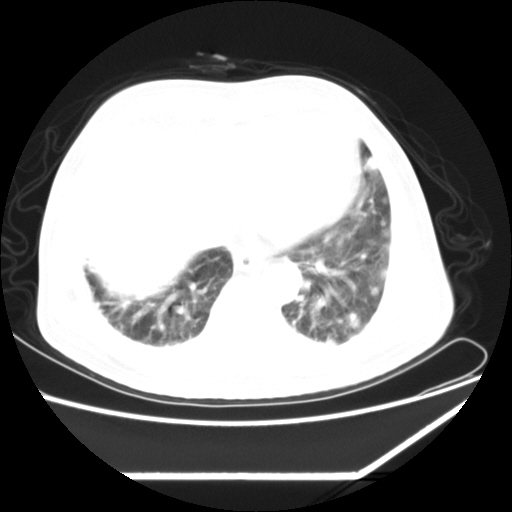

男,57,畏寒,发热

两肺野多发大小不一高密度灶,纵膈内见肿大淋巴结,要考虑转移瘤可能。双侧胸腔少量积液。

双肺多发结节样病灶,部分内见透光区,纵隔内见淋巴结肿大。结核临床如有畏寒,高热,白细胞增高首先考虑迁徙性肺脓肿(多是金黄色葡萄球菌感染)。

注意除外转移瘤。

双肺典型的亚急性粟粒性肺结核

双侧胸膜结核